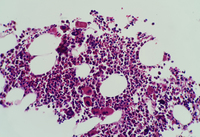

Idiopathic Thrombocytopenic Purpura - 2. Idiopathic Thrombocytopenic Purpura - 4. Immune Thrombocytopenia (ITP): Background, Pathophysiology, Etiology Giant thrombocyte in peripheral blood smear of an ITP patient ... Idiopathic Thrombocytopenic Purpura Smear